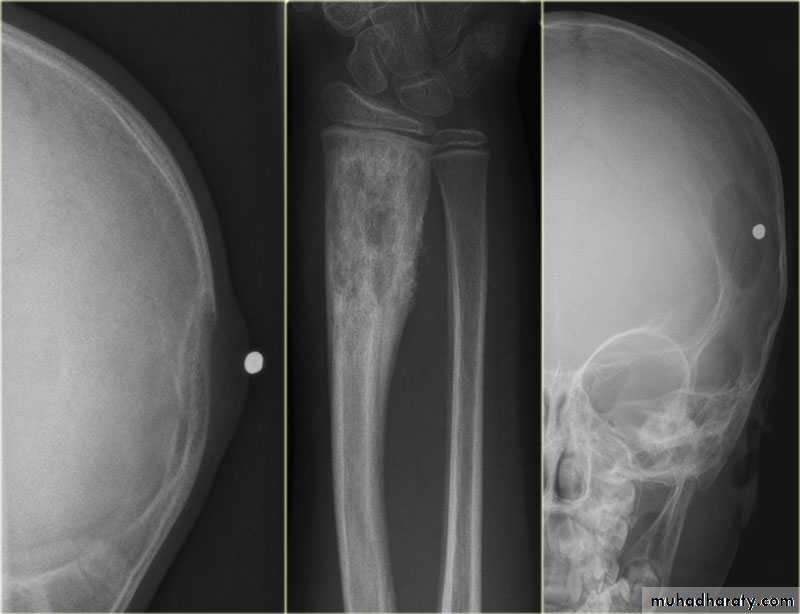

Primary malignant tumoursOsteosarcoma ( osteogenic sarcoma )

Chondrosarcoma :

Ewing sarcoma

Giant cell tumour

Benign tumour & tumour like condition

Enchondromas :Fibrous cortical defects ( non ossifying fibromas )

Fibrous dysplasia :